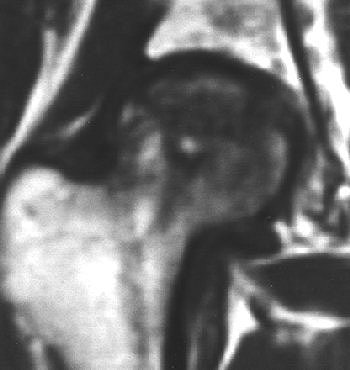

![]() |

| Right femoral head of 24-year-old woman who received high-dose steroid therapy for systemic lupus erythematosus. Coronal T1-weighted MR image (A) obtained 10 weeks after initiation of therapy shows band-like hypointense zone. Coronal STIR image shows matching hyperintense zones (B). Iida S, Harada Y, Shimizu K, Sakamoto M, Ikenoue S, Akita T, Kitahara H, Moriya H, "Correlation Between Bone Marrow Edema and Collapse of the Femoral Head," (AJR 2000; 174: 735-743). |

According to the results, 28% of the 46 hips had diffuse signal abnormalities in the marrow of the femoral head and neck. On T1-weighted images, these regions were ill-defined and decreased in signal intensity; on STIR images, they were diffusely hyperintense indicating bone marrow edema.

"Bone marrow edema was found in the living bone outside the band-like hypointense zone on the initial MR," the group stated. "At the time bone marrow edema was detectable on MR imaging, all 13 hips were symptomatic."

At final examination, 85% of these cases had progressed to advanced osteonecrosis, and bone marrow edema was highly correlated with the subsequent collapse of the femoral head.